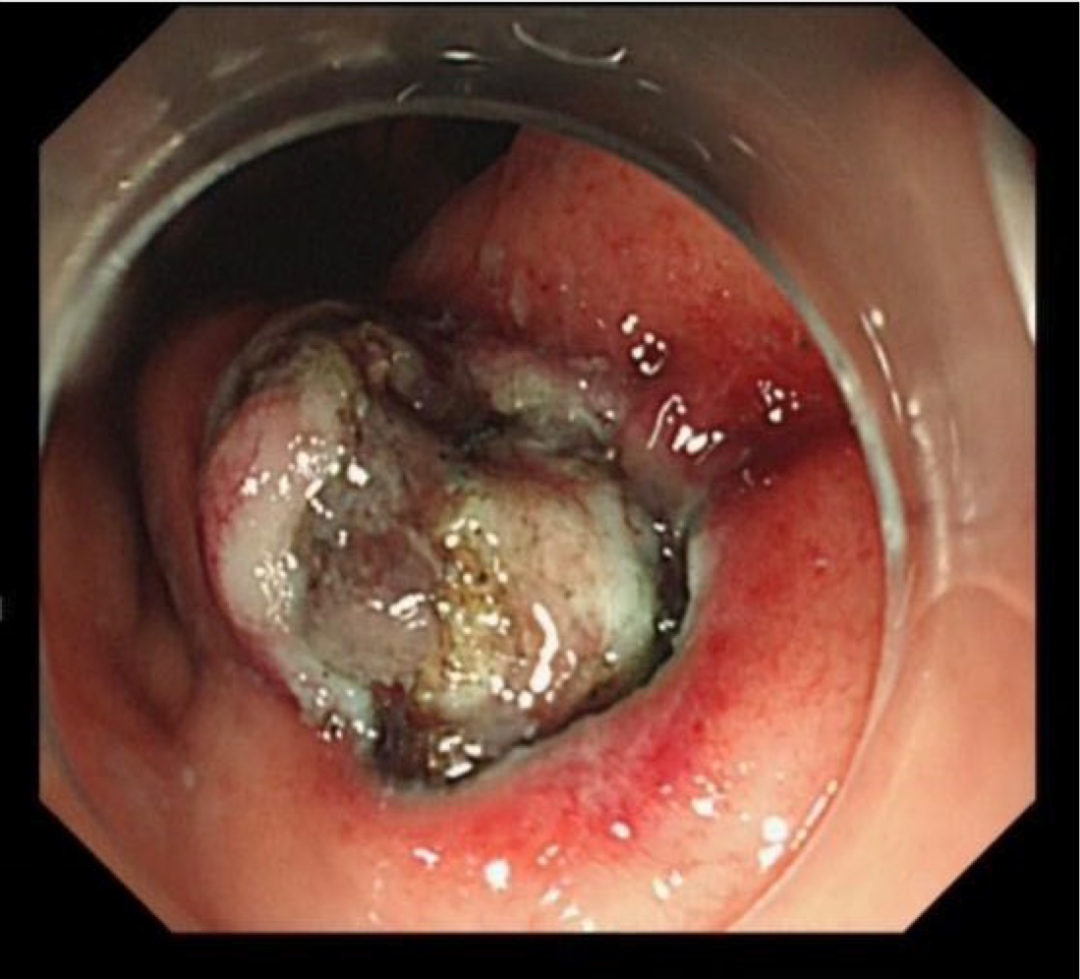

病例二:

赵某某,男,61岁,因“腹部不适伴大便次数增多2月余”入院,完善肠镜检查:直肠见一直径1.2cm 黏膜下隆起。超声内镜:直肠粘膜肌层低回声隆起,考虑神经内分泌肿瘤。

神经内分泌肿瘤有远处转移可能,与患者家属详细沟通、解释病情,完成充分的术前评估及准备后,孙院长实施黏膜下肿瘤挖除术,成功将病灶切除;术后病理诊断“神经内分泌肿瘤”,患者康复出院。